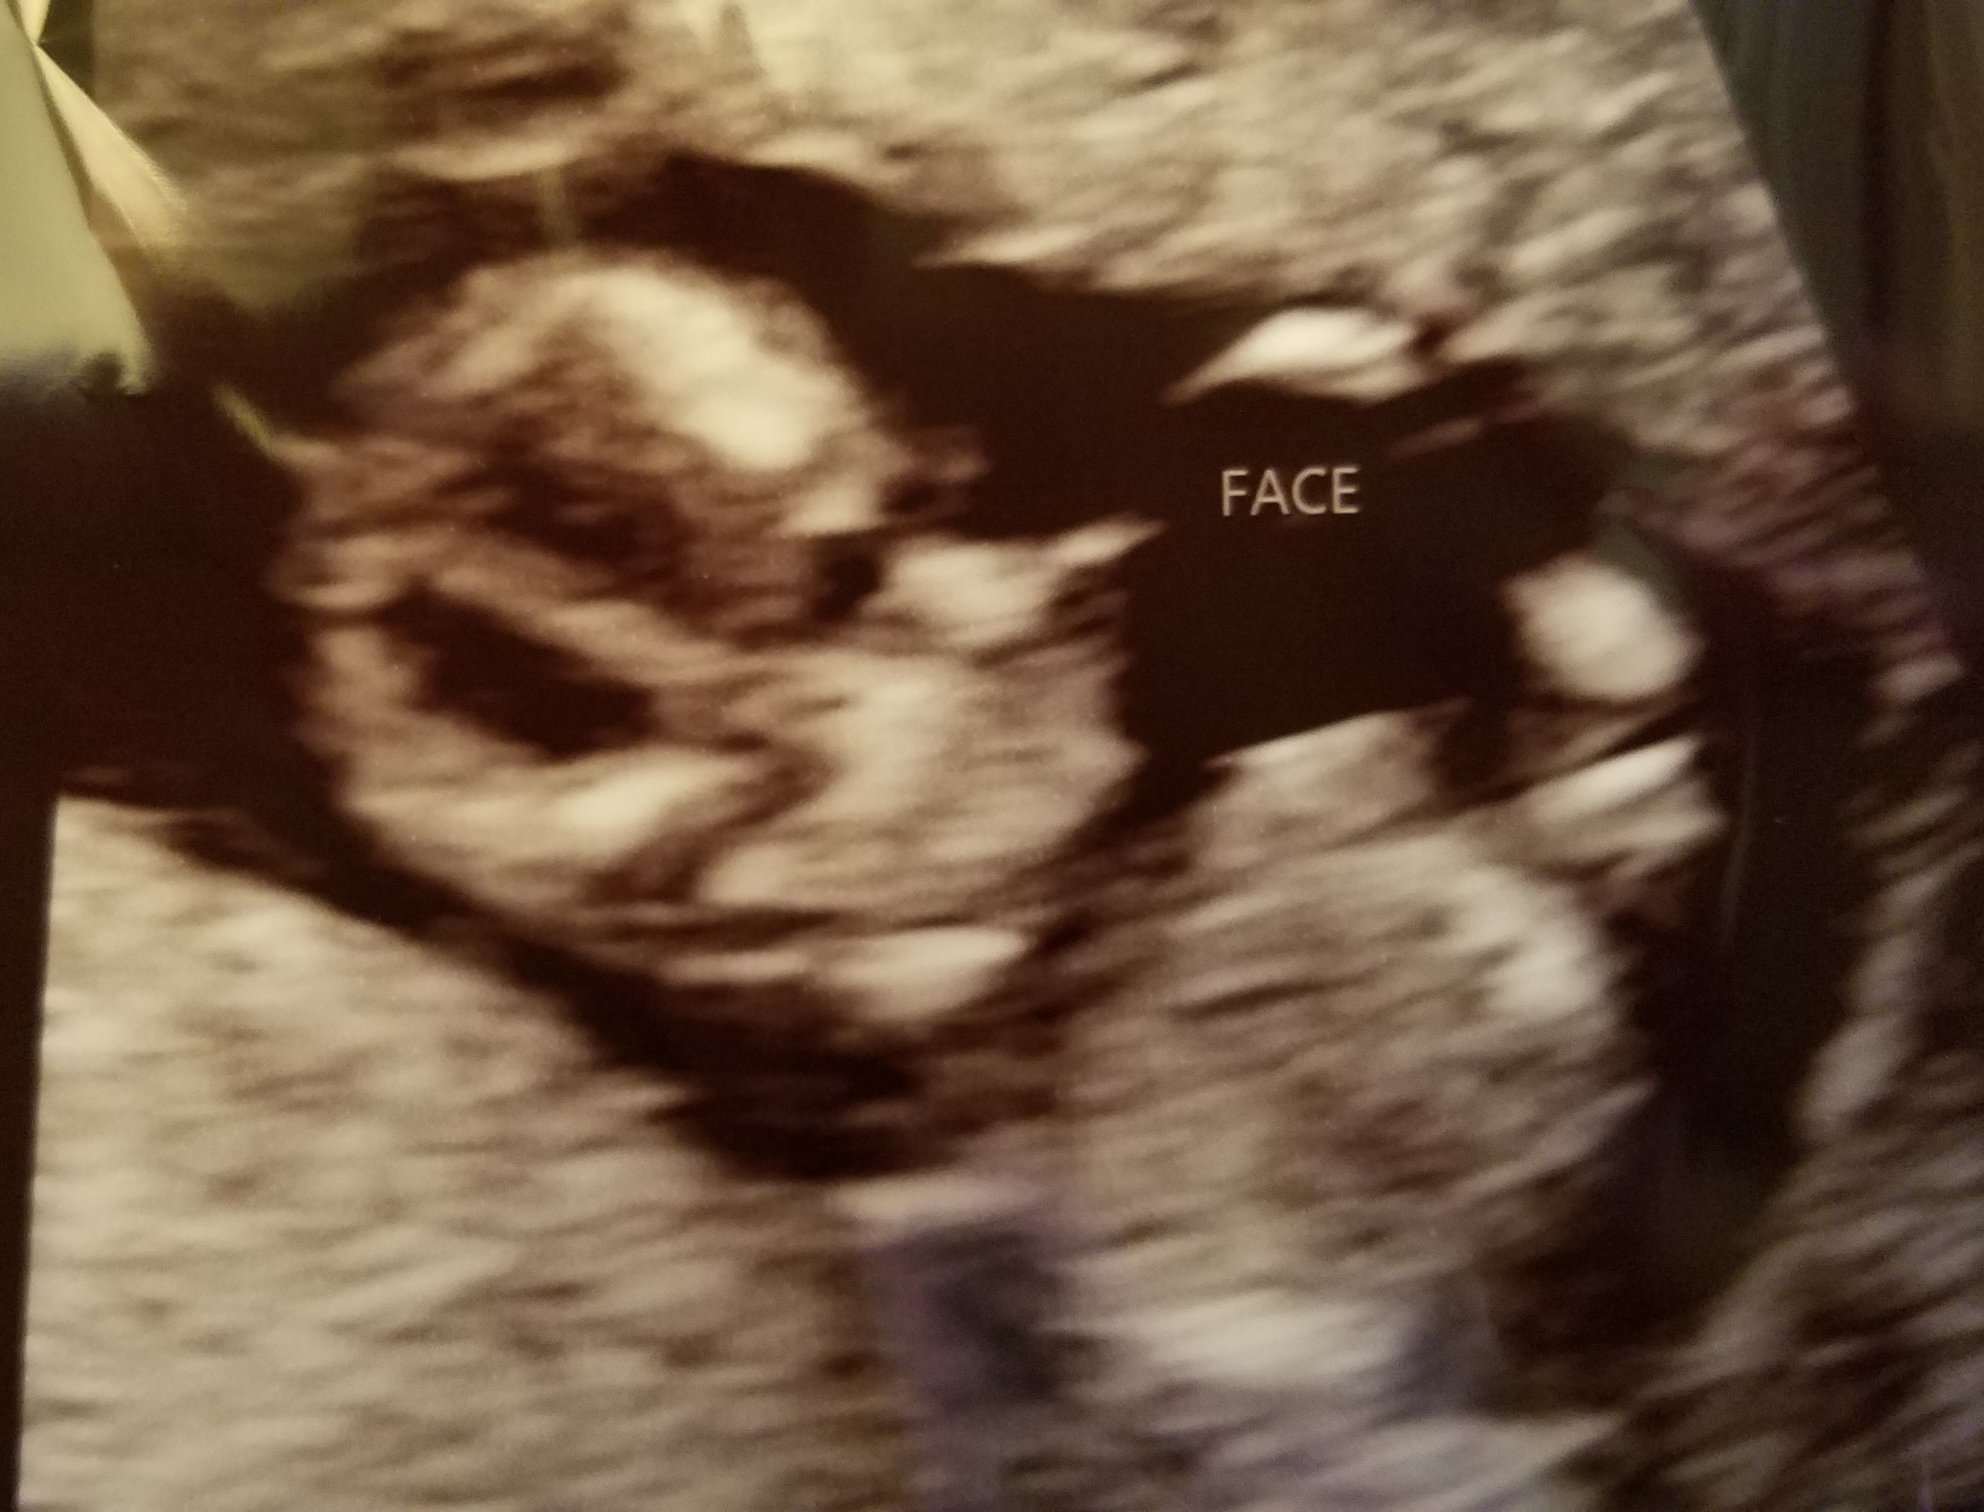

Blowing kisses - little cutie - NT scan turned out perfect! Looks like we're team pink- according to the doctors guess. 12w3days